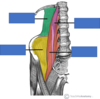

Red *

Trapezius

Innervation:

Motor - Accessory

Prorioceptive - C3,4

Action: Upper fibres - elevate and rotate during abduction middle fibres - retract lower fibres - depress

Yellow *

Latissimus dorsi

Innervation: Thoracodorsal nerve

Action: Extends, adducts and medially rotates upper limb

Green

Levator Scapulae

Innervation: Dorsal scapula nerve

Action: Elevation of scapula

Upper blue *

Rhomboid minor

Innervation: Dorsal scapula nerve

Action: Retracts and rotates scapula

Lower blue *

Rhomboid major

Innervation: Dorsal scapula nerve

Action: Retracts and rotates scapula